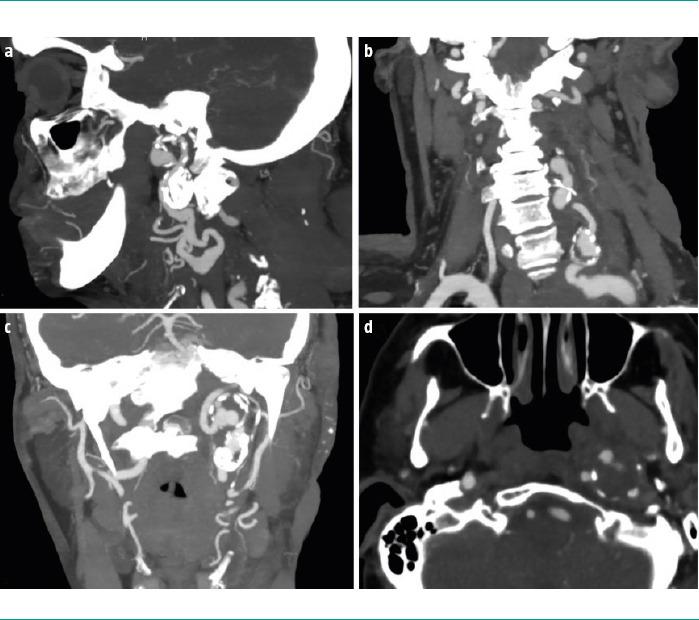

A 67-year-old woman with a genetic diagnosis of NF1 and a history of multiple exeresis of neurofibromas in the left cervical region. The patient presented with a painful flare-up and swelling in the region. A cervical magnetic resonance imaging was performed, which showed signs of plexiform neurinoma growth and a lesion suggestive of aneurysm in the left cervical internal carotid artery. A subsequent computed tomographic angiography confirmed the presence of a thrombosed aneurysm with associated critical stenosis, and identified three additional aneurysms in the proximal left vertebral artery. Given the asymptomatic presentation and adequate haemodynamic compensation, the patient was prescribed a conservative treatment and clinicoradiological follow-up.

一名67岁女性,基因诊断为NF1,有左侧颈部多个神经纤维瘤切除术史。患者该区域出现疼痛发作和肿胀。进行了颈部磁共振成像检查,显示有丛状神经鞘瘤生长迹象以及左侧颈内动脉有一个提示动脉瘤的病变。随后的计算机断层血管造影证实存在一个血栓形成的动脉瘤并伴有严重狭窄,且在左侧椎动脉近端发现另外3个动脉瘤。鉴于患者无症状表现且血流动力学代偿良好,对其进行了保守治疗及临床影像学随访。